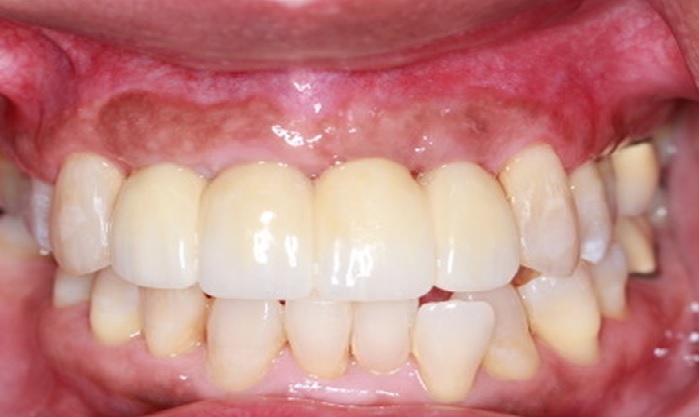

Patient 2 - After

Post treatment patient presentation following gum surgery, implant placement and restoration with crowns.